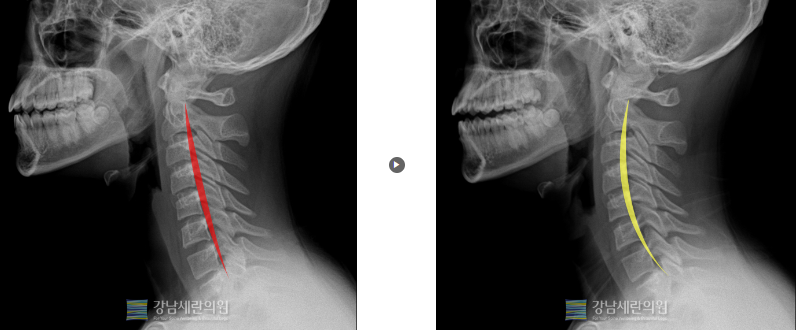

#일자목

일자목 교정 전 ▶ 일자목 30회(3개월) 치료 후